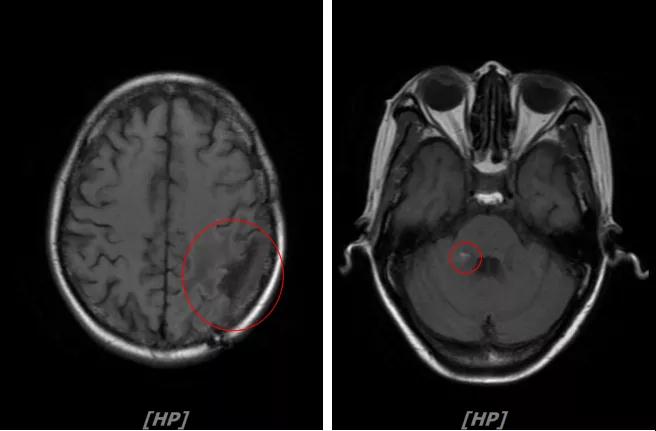

4.病情第3次进展:2018年10月患者头痛症状又加重

头颅增强MR:左侧顶颞叶见片状T1WI低信号、T2WI高信号影,病灶大部信号接近脑脊液;增强后可见左侧额叶、顶叶、两侧海马及右侧小脑半球呈多发斑点状、结节样明显强化,大者大小约14x11mm,较2016-12-11增强老片病灶增大、增多;两侧半卵圆区、侧脑室旁见较对称片状T1WI低信号、T2WI高信号影,增强后未见明显强化( 较2017-8-9MR老片稍明显) ;余脑室、脑池、脑沟大小形态可,中线结构居中无移位。左侧上颌窦粘膜轻度增厚

左顶颞叶转移瘤治疗后改变;脑内多发强化灶,考虑转移,较前增大增多

两侧脑室旁云絮状异常信号:考虑放疗后改变

患者二线治疗的PFS为22个月,2018年11月患者给予后续解救治疗为吡咯替尼(400mg/d)联合阿那曲唑;患者头痛症状好转,病灶继续缩小,继续定期复查。